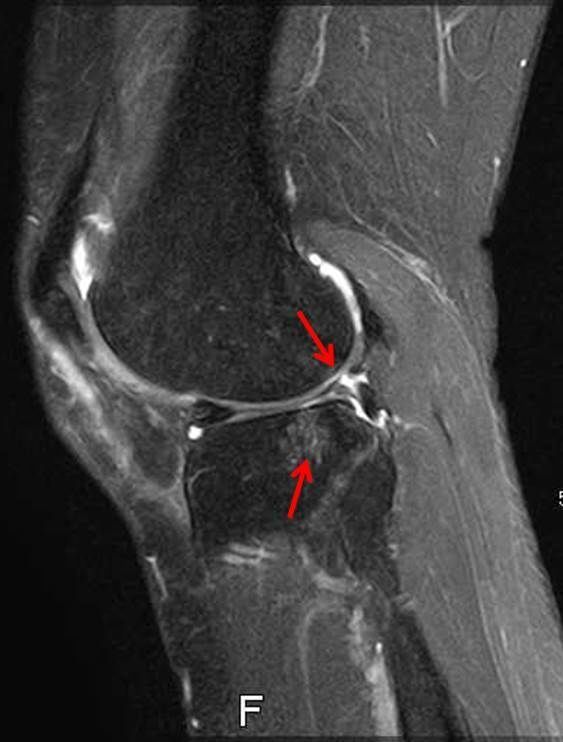

画像所見

| レントゲン | MRI | |

| 骨傷なし、骨棘あり Kellgren-Lawrence分類gradeⅡ | 外側半月板のフラップ損傷あり 骨損傷あり | |

外側半月板と軟骨損傷の治療はなかなか難しいですね。術前に半月板断裂部が嵌頓してロッキングしている症状なのか軟骨損傷によるものなのか完全に把握するのは難しい時もあります。

今回は軟骨損傷により剥がれた軟骨片や半月板の断裂によるフラップ部分の引っ掛かりとそれにより膝の伸びが完全に出ないのが一番の問題と捉えて関節鏡視下手術を施行しました。術後膝が伸びないのが後方の筋腱拘縮の問題もありリハビリテーションも効果がとてもありました。